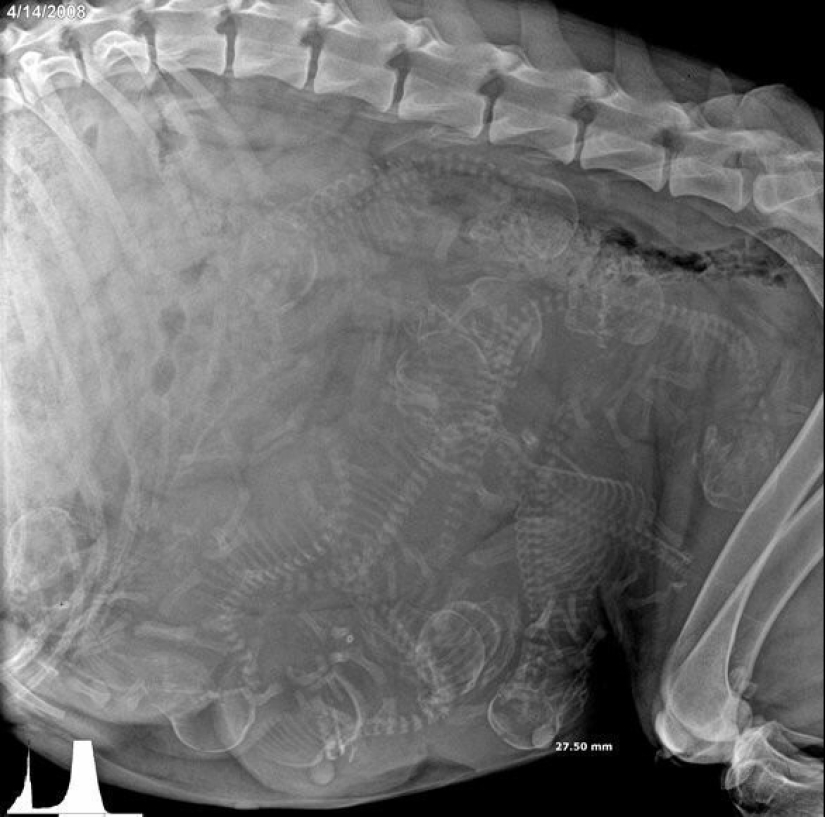

Pregnant dog